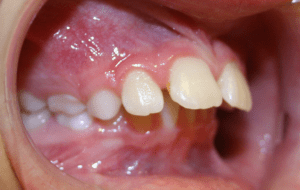

Before and After photos: Crossbite Treatment

Crossbite

A crossbite occurs when one or more of the upper teeth bite on the inside of the lower teeth. It can occur in the front of the mouth or on the sides, where its usually a bilateral condition. Early correction of a crossbite is recommended because it can lead to permanent problems including asymmetric jaw growth, irregular muscle function and altered tooth eruption.

Crossbite should be corrected because it can:

- cause premature wear of the teeth

- cause gum disease including bone loss

- cause asymmetrical development of the jaws

- cause dysfunctional chewing patterns

- make your smile less attractive

If there is a single tooth in crossbite, the tooth can be moved into the correct position with braces. When multiple teeth are in crossbite, the arch needs to be expanded with braces or a combination of braces and an intra-oral appliance. This will help correct the bite relationship and allow the jaws to grow in harmony.